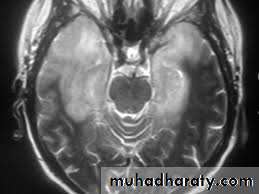

17 years old girl brought to A&E with severe agitation and speaking non sense, sustained three fits each preceded by abnormal sense of smell for few seconds. O/E there was mild neck stiffness, Kernig sign was negative. However she was Dilerious. CSF showed protein 67 mg/dl, sugar normal, cells 10 WBC, all lymphocytes. Gram stain negative.EEG reveals bilateral temporal spikes and MRI picture shown below. What is the diagnosis:Differential Diagnosis